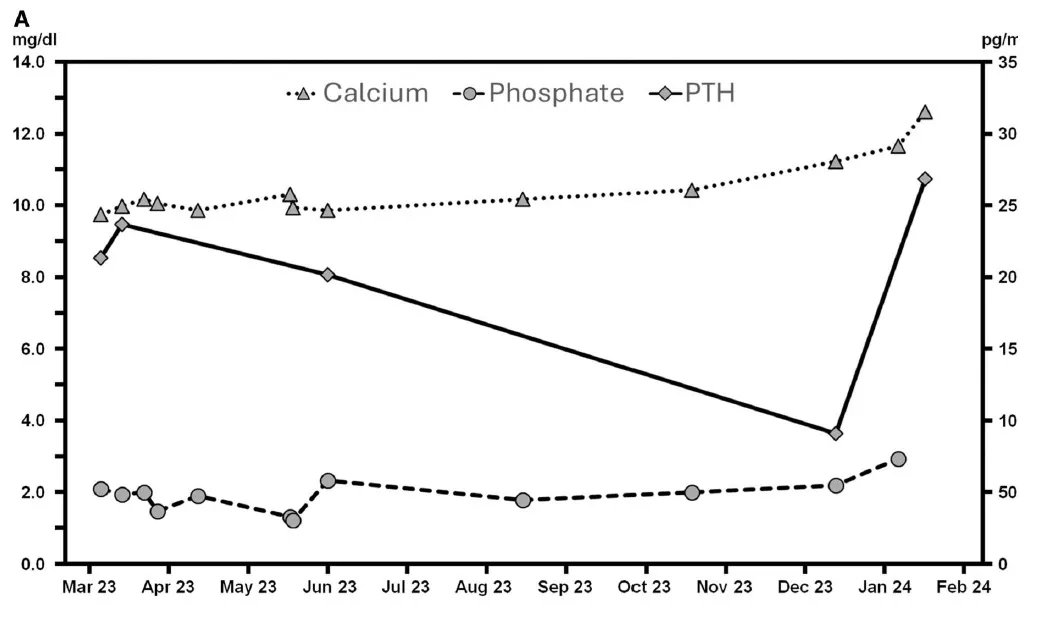

medicamentos. Recentemente, o paciente tinha apresentado hipercalcemia progressiva com hipofosfatemia concomitante e níveis elevados de paratormônio (PTH).

Changes in the levels of total calcium, phosphate, and intact PTH in the months before admission (reference range: calcium 8.8–10.2 mg/dl; phosphate 2.5–4.5 mg/dl; PTH 15.0–65.0 pg/ml).

Quatro semanas antes da admissão, ele teve uma infecção por COVID-19 que se resolveu em casa, seguida por sintomas como perda de apetite, saciedade precoce e dor epigástrica. A suspeita inicial era de hiperparatireoidismo terciário, e o tratamento com cinacalcete foi iniciado. No entanto, duas semanas antes da admissão o paciente piorou, desenvolveu febre intermitente e a hipercalcemia piorou, resultando em deterioração rápida do estado clínico.

* Hipercalcemia (cálcio total de 12,64 mg/dL) com altos níveis de vitamina D ativa (102 pg/mL), PTH intacto elevado (269 pg/mL) e baixos níveis de 25-hidroxivitamina D (12,2 ng/mL)

A hipercalcemia devido ao hiperparatireoidismo persistente é comum no primeiro ano após o transplante

renal. PJP e citomegalovírus são complicações infecciosas graves, embora sua prevalência tenha sido reduzida com o uso de tratamentos profiláticos como valganciclovir e trimetoprima/sulfametoxazol. A hipercalcemia associada à PPJ está sendo cada vez mais relatada em pacientes transplantados renais, e

acredita-se que a conversão aumentada de vitamina D nativa para ativa por macrófagos ativados em tecido granulomatoso seja o principal mecanismo patogênico. Os achados laboratoriais deste caso - hipercalcemia, altos níveis de vitamina D ativa e baixos níveis de 25-hidroxivitamina D - são consistentes com essa hipótese.